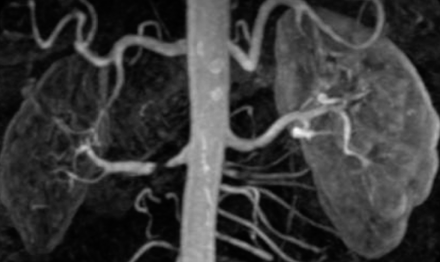

- If it comes to 20y/o man, what is the cause? Z Secondary HTN

- Name 2 etiologies of condition: Z Atherosclerosis, Fibromuscular dysplasia

- Pathology in the image: Renal Artery Stenosis

- Treatment option: Angioplasty + or - stent